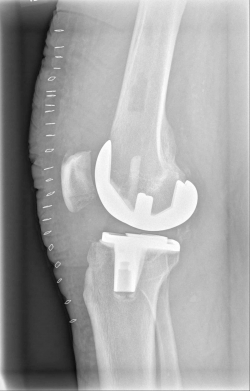

Example X-ray images before and after implantation of a Persona knee prosthesis with robot.

Röntgenbild nach OP von vorn Röntgenbild nach OP von seitlich

b) nach Implantation der Knie-Totalendoprothese angefertigte Röntgenaufnahmen